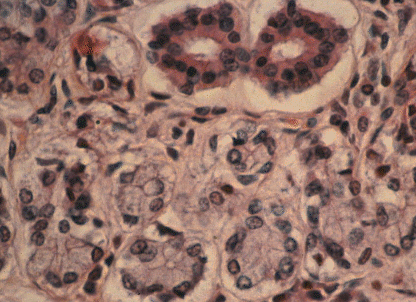

This shows the histological structure of a very small part of a salivary gland. Salivary glands are compound tubuloalveolar, which simply means they are formed from tubes and balloons. The two things that look like doughnuts at the top are two sections through ducts or tubes. The rest of the picture is filled with pale alveoli, the balloons where the saliva is produced. The nuclei (pale blue) of the salivary cells lining the alveoli can be seen.